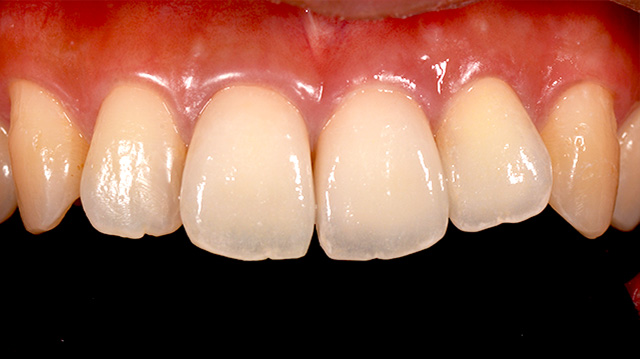

| 年代・性別 | 40代 男性 |

|---|---|

| 主訴 | 前歯の色が気になる |

| 治療回数 | 3回 |

| 治療期間 | 約1ヶ月 |

| 費用 | 仮歯 5,500円 ジルコニアクラウン 176,000円 |